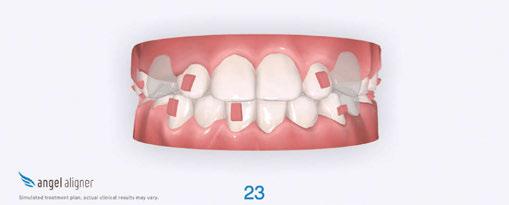

Treatment progression

The primary phase of treatment had a total of 20 sets of aligners, and we saw the patient for three appointments (Figure 4). His compliance with aligner wear and tracking was excellent. We were pleasantly surprised by how well he adapted to both the aligners and attachments, especially given his severe oral sensitivities.

Figure 2A (top): Initial set-up in iOrtho. Figure 2B (bottom): Superimposition view of the initial set-up in iOrtho

Figure 4: JA refinement records 4 months into treatment (10.11 years old). Upper and lower expanded. Refinement goals were to complete alignment and space consolidation and exaggerate U2 mesial root tip